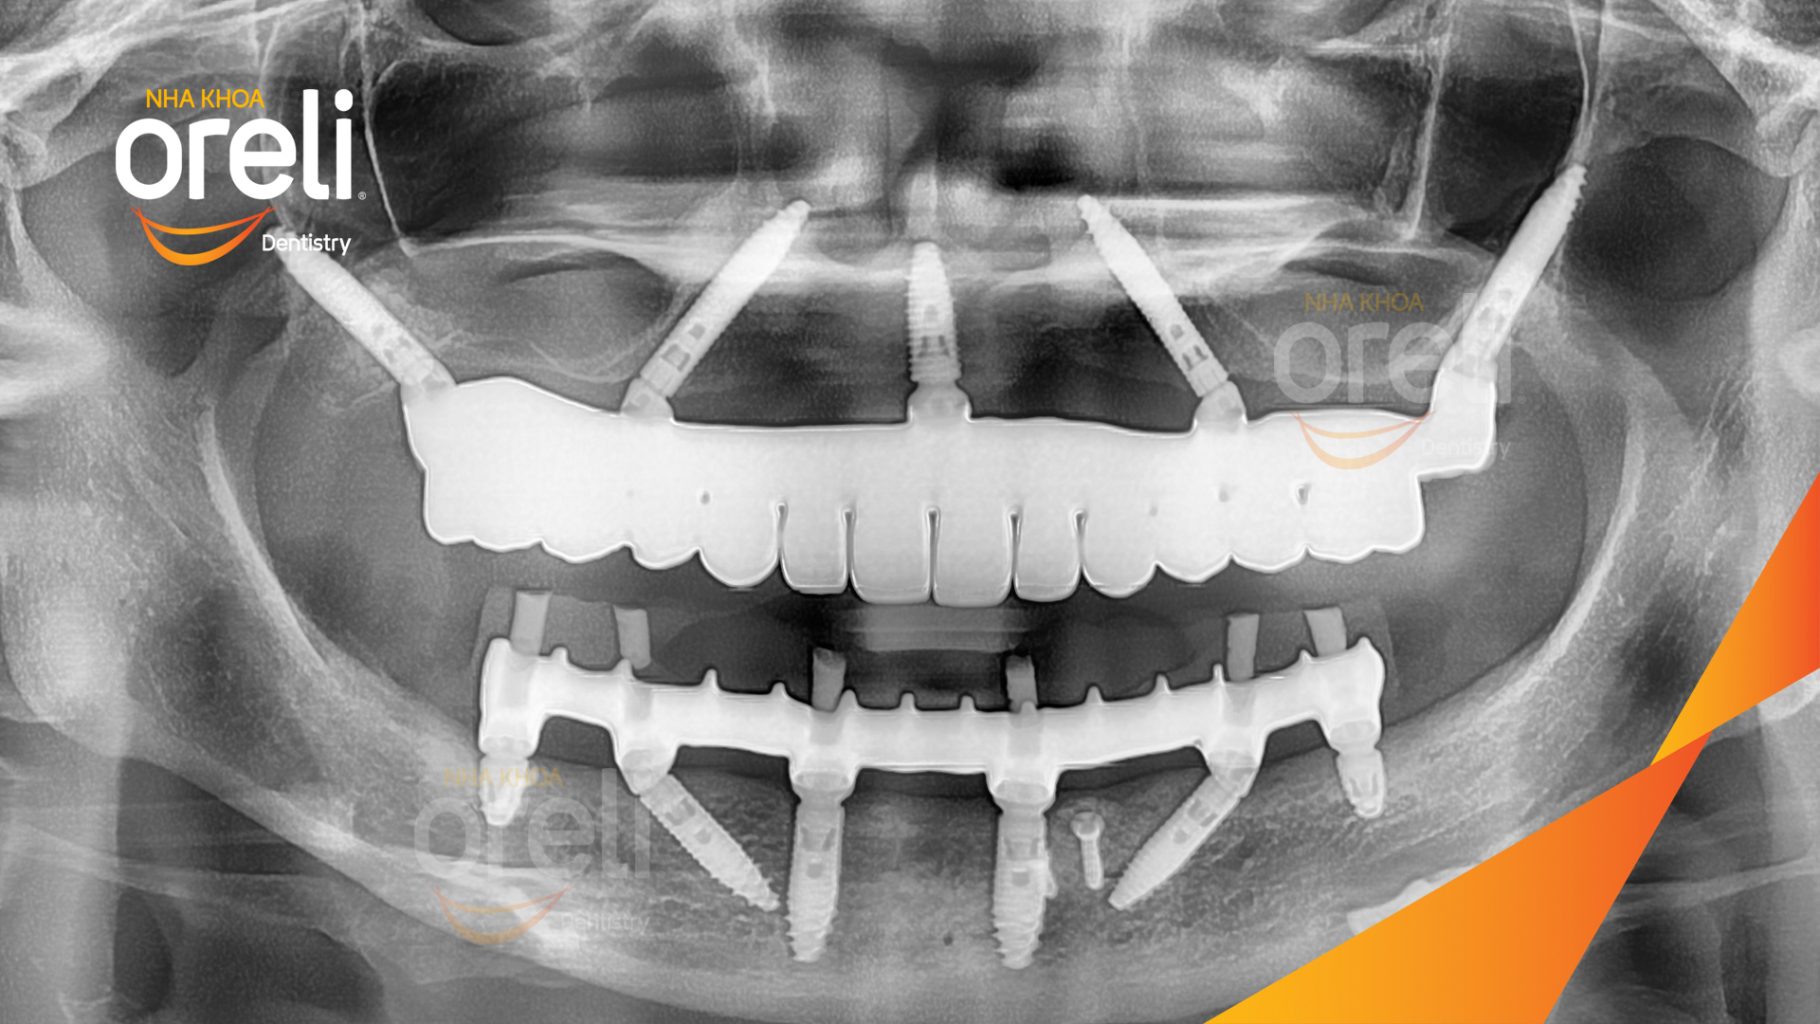

Giải pháp: Cắt bỏ cầu sứ nhổ răng lung lay, cấy ghép răng implant hàm trên và dưới

Kết quả: Chị khách cười nói tự tin và ăn nhai chắc chắn

Hình ảnh thực tế